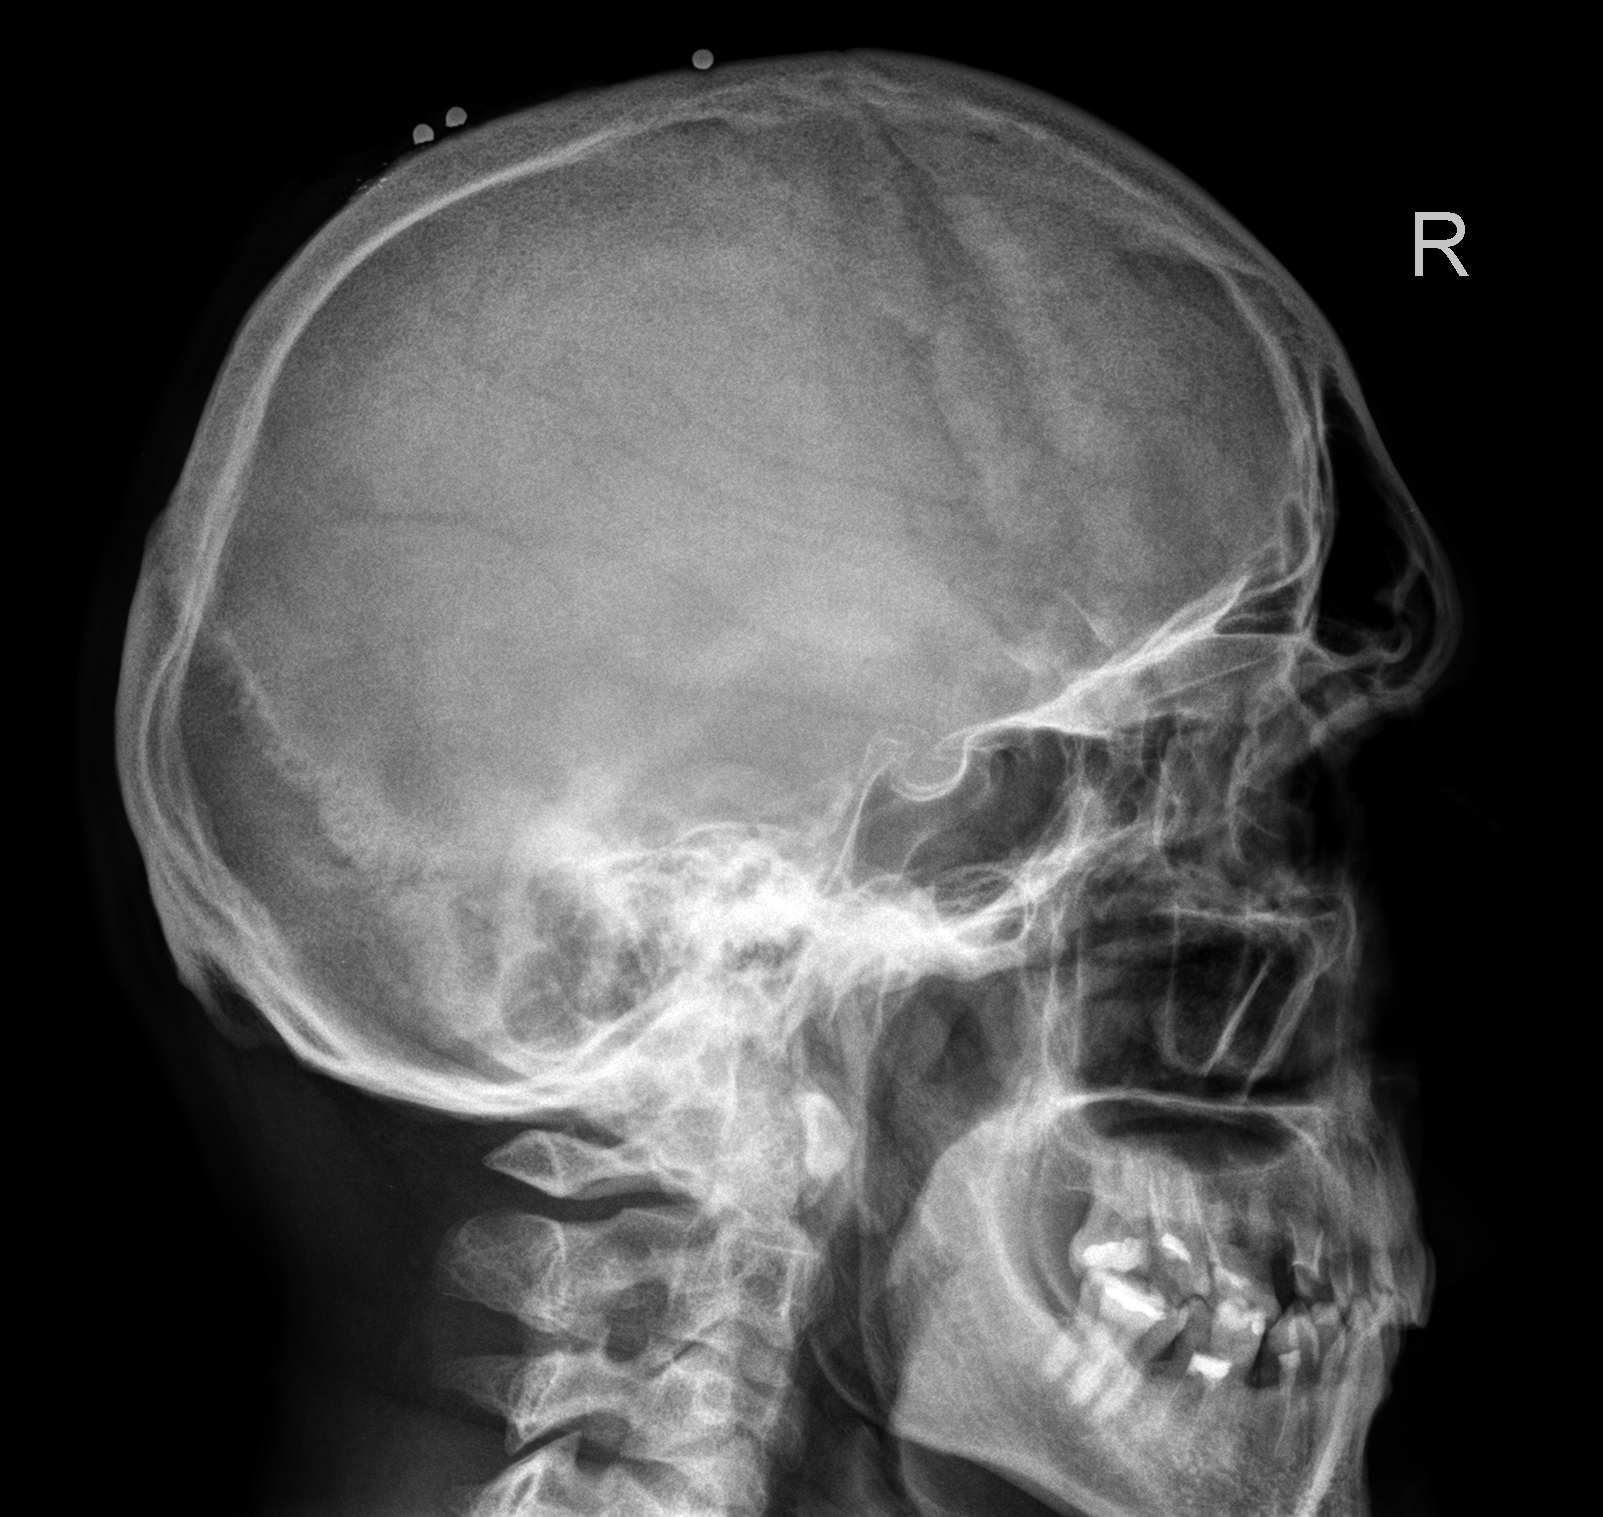

Анатомия детского черепа: Рентгеновские снимки и описание